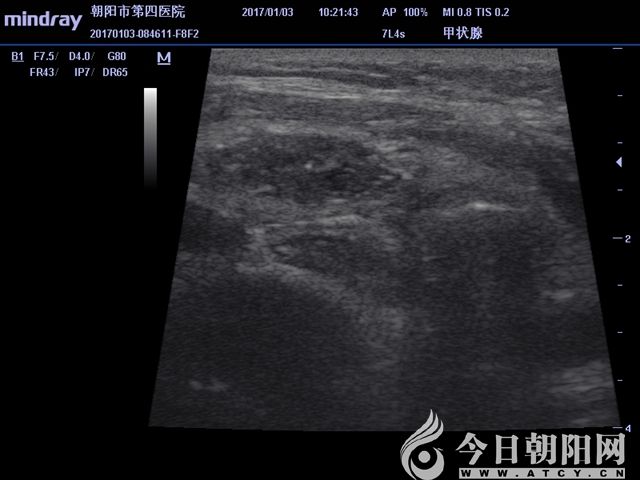

抽液后超聲顯示實性結節(jié)

抽液后超聲顯示實性結節(jié)范圍

微波消融針穿刺至實性病變處,根據超聲引導,調整消融針,連續(xù)消融,至病變區(qū)域全部達到熱容效應?;颊咴谑中g中始終保持清醒,無明顯疼痛等不適感,偶有咽喉部輕度的腫脹感。術后4小時,患者離床活動,飲水無嗆咳,聲音無嘶啞。術后第3天,患者恢復良好,現(xiàn)已出院。